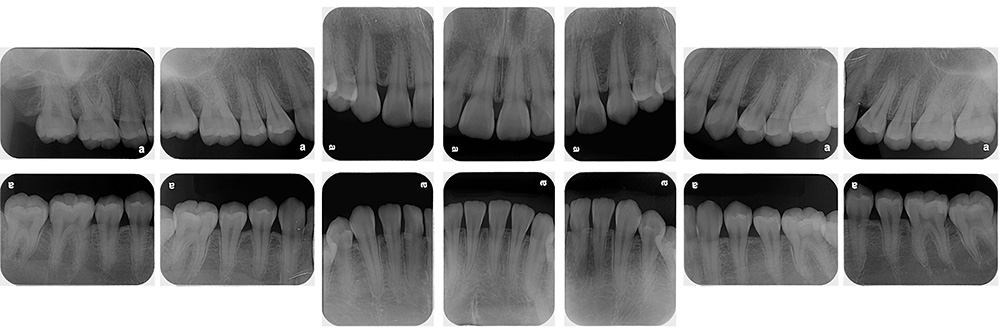

術前

術後

世代・性別

60代男性

主訴

歯ブラシで出血するので見てほしい

治療内容

ブラッシング指導、歯周基本治療、虫歯治療、根管治療、補綴治療

治療期間

6ヶ月

治療費

保険適応内

治療のリスク

治療後にしみる・痛みが出ることがある